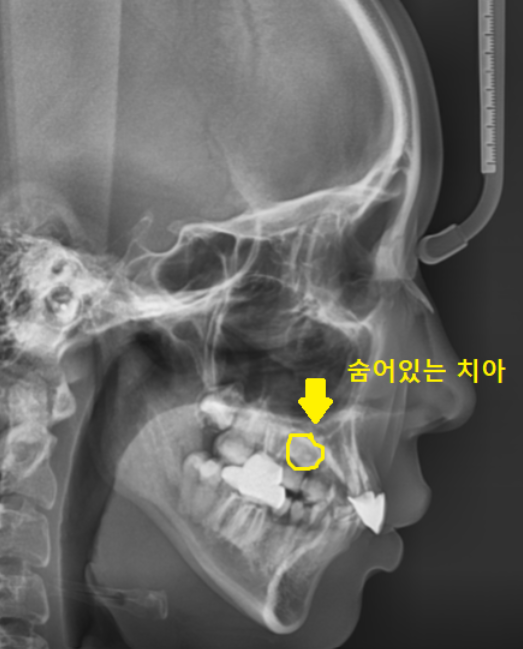

처음 저희 병원을 방문하셨을 때의 사진입니다.

교정하기 위해서는 발치를 해야하는데

대학병원에 가셔서 뽑고 오셔야한다고 들으셨대요.

구강 상태를 보실까요~?

나와야할 영구치가

잇몸 안에 묻혀서

나와있지를 않네요~

완전히 묻혀있다 하여

완전 매복치라고 표현합니다.

교정 진단을 위해 촬영한 사진에서도

숨어있는 매복치 보이시죠~?